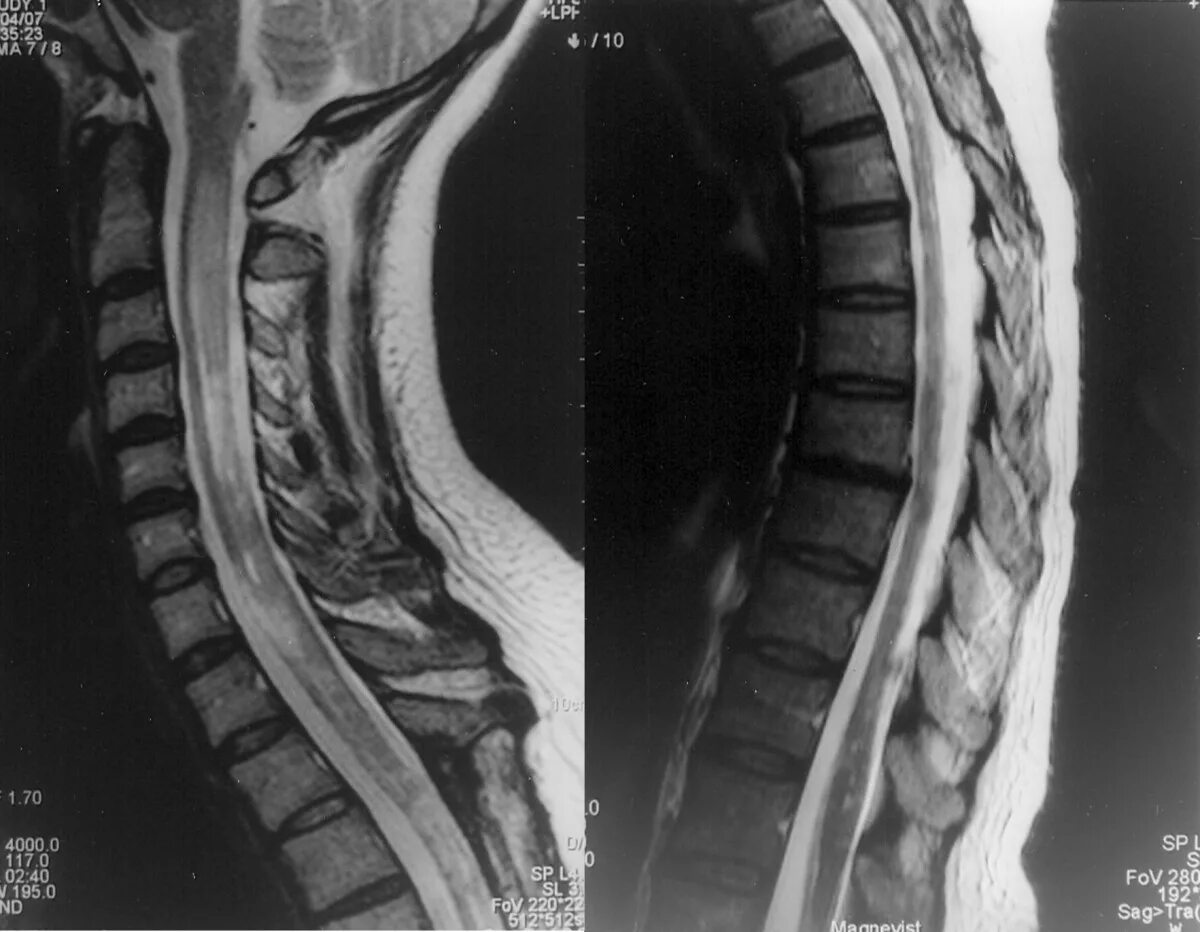

Spine mri